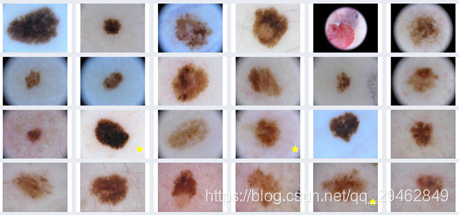

十、Isic Archive(黑色素瘤)

数据下载链接:https://github.com/GalAvineri/ISIC-Archive-Downloader

数据介绍:该档案库包含分类皮肤损伤的23k图像。 它包含了恶性和良性的例子。每个示例均包含病变的图像,有关病变的元数据(包括分类和分割)以及有关患者的元数据。